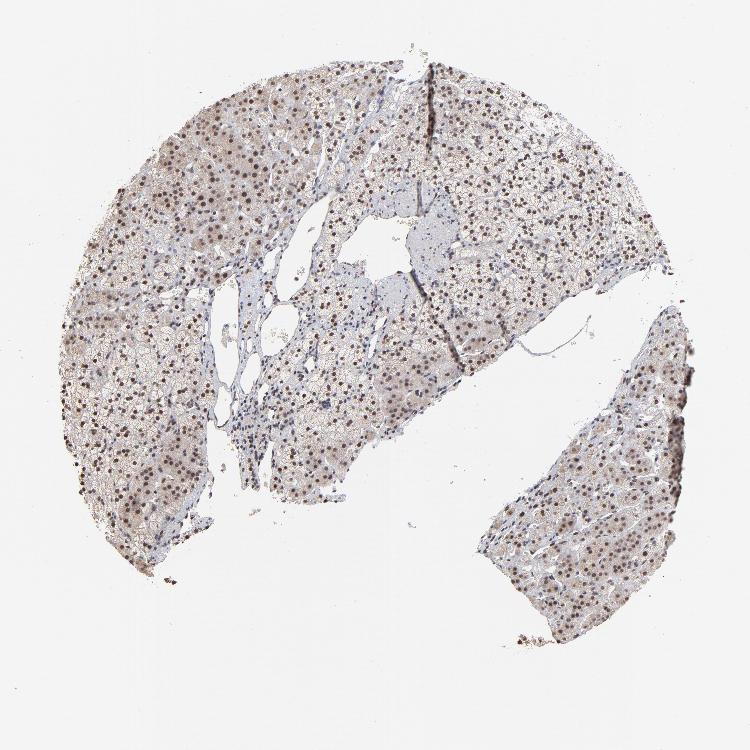

ADRENAL GLAND - Antibody stainingi

Antibody staining in the annotated cell types in the current human tissue is reported as not detected, low, medium, or high, based on conventional immunohistochemistry profiling in selected tissues. This score is based on the combination of the staining intensity and fraction of stained cells.

Each image is clickable and will lead to virtual microscopy that enables deeper exploration of all samples and also displays staining intensity scores, fraction scores and subcellular localization as well as patient and tissue information for each sample.

Antibody HPA002813

Glandular cells Medium